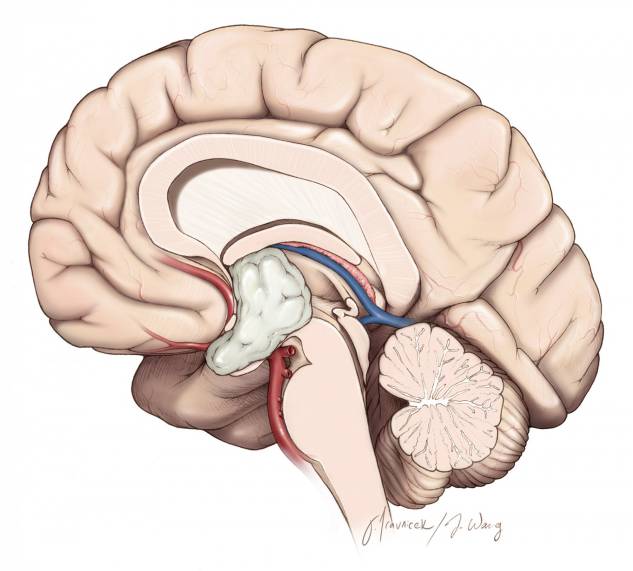

本章关注的特定区域是三脑室的前部,它大约位于视交叉和Monro 孔之间的部分空间。其边界包括视交叉、终板、前联合和穹隆柱。

图2. 图示一例三脑室前部鞍上脊索样胶质瘤。该病例既往在其他医疗机构采用经额叶皮层入路手术。因为该手术入路的工作角度受限,最后不得不放弃全切。笔者在离断透明隔静脉后采用了经胼胝体-经扩大室间孔-经静脉入路最后分离并切除了前方脊索样组织。注意视交叉位于肿瘤下方(黄色箭头)和经终板的狭小空间。这些特点限制了经鼻和经额下手术入路。

笔者切除三脑室前部和中部肿瘤时优先选择经胼胝体-经扩大室间孔-经静脉入路。如果肿瘤无法内镜下经鼻经终板入路切除,笔者就选择经胼胝体-经扩大室间孔-经静脉入路。这二种入路能处理95%以上的三脑室肿瘤,大多数三脑室颅咽管瘤因其存在鞍上黏连而更适合采用经鼻入路。

不伴有终板池扩大的大而硬、实体肿瘤和血运丰富的肿瘤,采用经胼胝体-经扩大室间孔-经静脉入路显露更有效率。